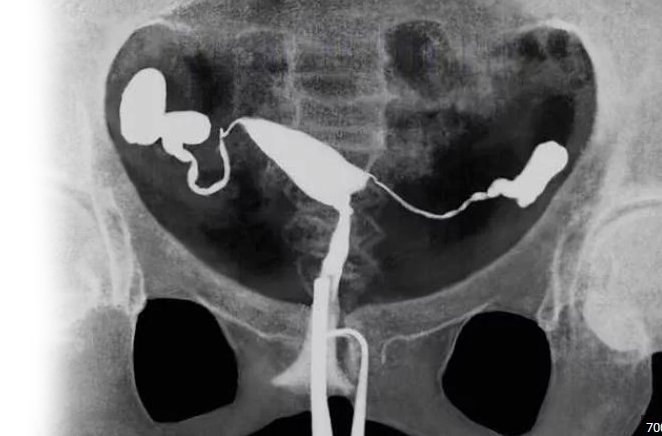

Гистеросальпинография – важный метод рентгенологического обследования матки и маточных труб на наличие в них патологических изменений. В ходе проведения рентгена маточных труб, матка и маточные трубы заполняются рентгеноконтрастным веществом и подвергаются небольшой дозе ионизирующего излучения.

Гистеросальпинография маточных труб позволяет определить их длину, структуру, проходимость маточных труб. Все эти нарушения могут способствовать невозможности зачать ребенка, поскольку причиной могут быть спайки маточных труб. Эта патология возникает при наличии воспалительного процесса, либо как следствие предыдущих оперативных вмешательств.